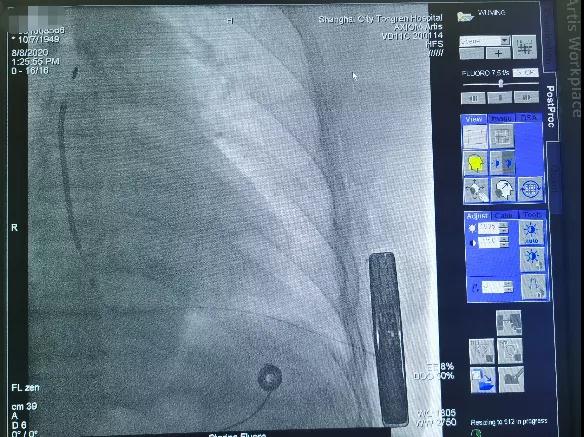

手术在全麻醉下进行,于左侧第5肋间沿腋中线走形切开皮肤6厘米,逐层分离皮下组织至肌层,寻找到背阔肌与前锯肌之间的深筋膜层,钝性分离,做好囊袋确保足够深度来容纳装置。

于剑突下切开皮肤2cm,逐层分离皮下组织至筋膜层,通过隧道穿引针连接囊袋,再沿胸骨向上约14cm处切开皮肤1cm,逐层分离皮下组织至筋膜层,通过隧道穿引针连接剑突下切口,使用隧道穿引针将45cm长的3501除颤电极从囊袋经隧道送至剑突下切口,固定电极中段,再使用隧道穿引针将电极经隧道送至胸骨上方切口,固定头端。连接脉冲发生器A209,置入囊袋内,逐层缝合筋膜层及皮下组织,进行DFT测试,采用50HZ,200MA交流电方式进行诱颤,SICD正确识别,经首次65J除颤成功,除颤阻抗58欧姆。缝合皮肤 ,术区纱布覆盖,包扎,弹力绷带加压包扎止血。手术圆满成功,耗时约1小时。